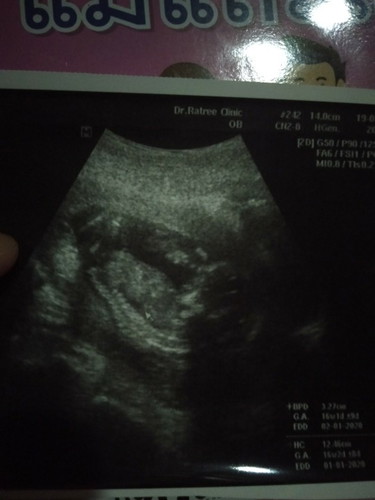

อยากจะถามแม่ๆว่าพอจะรุไหมว่าเปนเพศไหนพอดีท้องแรกดูไม่เปนอ่ะค่ะ